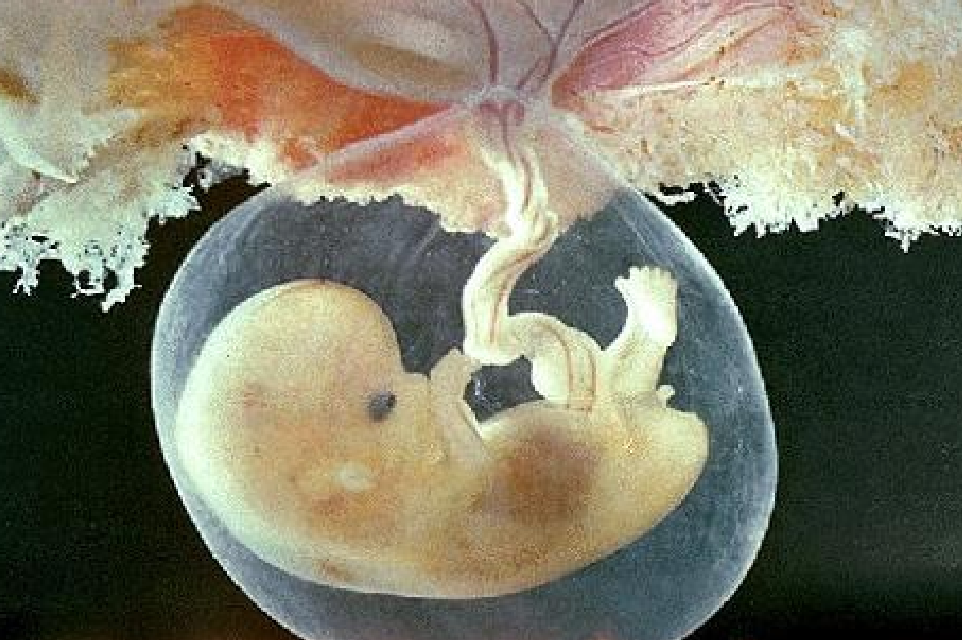

¿Qué es el DPPNI (Desprendimiento Prematuro de Placenta Normoinserta)?

Cara materna, con los cotiledones

Desprendimiento parcial o total de la placenta de su inserción normal antes del parto, con formación de un hematoma por rotura de vasos de la decidua basal.